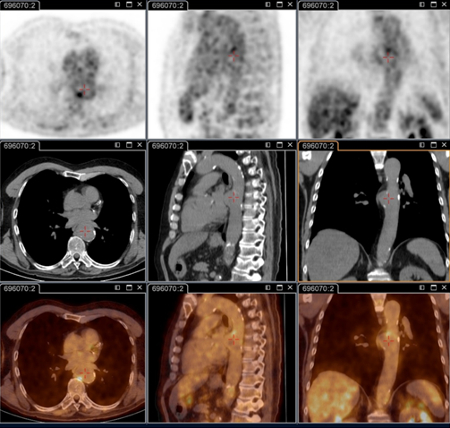

Q fever aortic mycotic thoracic aneurysm diagnosed at PET scan: 18F-fluorodeoxyglucose PET/CT. In this asymptomatic patient with heart valve history with elevated serology, the PET scan diagnosed an aortic endocarditis on native valve with thoracic and lumbar aortic mycotic aneurysms

Institut Hospitalo-Universitaire Méditerranée Infection (patient consent obtained)